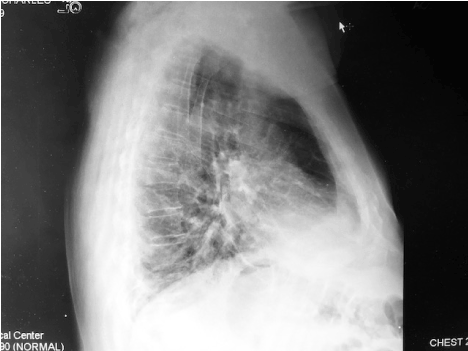

A chest x-ray showed an indistinct right basilar density with a potential small effusion possibly related to atelectasis or pneumonia (Figures 1A and 1B). There were no evident rib fractures.  While preparing for a chest CT, the patient coughed, and the bulge recurred.  CT images showed a large herniation of the right lower lobe between the 9th and 10th rib interspace. The adjacent ribs were separated with interruption of the associated intercostal muscles (Figures 2A and 2B, Figure 3 and Figure 4).

Figure 1B. Admission chest X-ray, lateral view.